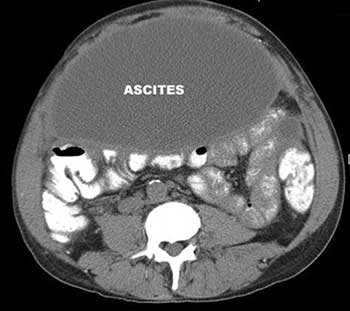

Асцит — патологическое состояние, при котором в брюшной полости скапливается жидкость. Причины его бывают различными. Чаще всего к асциту приводит цирроз печени. Так же он возникает как осложнение онкологических заболеваний, при этом ухудшается состояние больного, снижается эффективность лечения.

Если в брюшной полости скапливается небольшое количество жидкости (100-400 мл), симптомы отсутствуют. В таких случаях асцит обнаруживают зачастую случайно во время УЗИ или КТ органов брюшной полости.

Внешние признаки асцита становятся хорошо заметны, когда количество жидкости в брюшной полости достигает 0,5-1 литра. Живот при этом заметно увеличен. Когда пациент стоит, он выглядит отвисшим, в положении лежа — распластан, боковые его части выступают. Врачи называют такую картину образно «животом лягушки».

Водянка начинается с небольшого объема жидкости, о которой больной даже не подозревает. Первичное скопление хорошо прослеживается при ультразвуковом обследовании.

Когда концентрация жидкой субстанции достигает 1 л, живот заметно увеличивается. С набуханием объема нарастает характерная симптоматика:

Асцит, или брюшная водянка - это вторичное патологическое состояние, характеризующееся накоплением жидкости в свободной брюшной полости. Данная патология может наблюдаться при многих первичных заболеваниях, например, при полисерозите, циррозе печени, панкреатите и так далее. Всем пациентам с впервые выявленным асцитом проводится такая диагностическая манипуляция, как лапароцентез. В этой статье мы поговорим о том, что такое лапароцентез брюшной полости при асците, показаниях и технике его проведения.